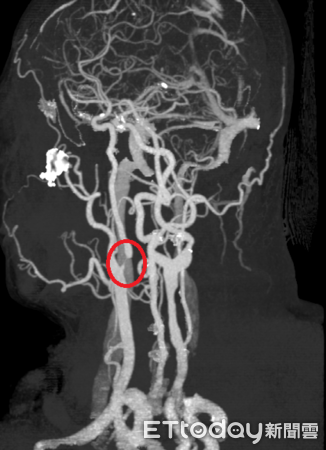

▲頸動脈狹窄影像圖。(圖/衛福部南投醫院提供,下同)

50歲林姓男子近日因不時感到頭暈、左邊手腳麻而就醫檢查,經神經內科醫師初步安排電腦斷層檢查,雖未發現明顯中風跡象,但基於臨床警覺,進一步安排頸動脈超音波檢查,結果發現內頸動脈已有狹窄情形,隨即收治住院觀察,並轉介神經外科醫師接受內頸動脈血管成形術(氣球擴張合併支架置放),成功改善腦部血流,術後恢復良好、已康復出院。

陳奕安說明,前述病患術後需長期服用抗血小板的藥物,以預防血管再次阻塞,並須配合定期追蹤檢查,確保血管通暢。